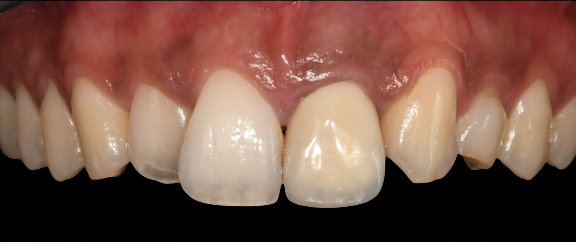

Step 6 — Immediate temporary restoration. A VARIOtemp abutment was placed, and a screw-retained temporary crown (designed by the lab in Dentalwings software and milled pre-operatively) was fitted immediately. A tunneling technique with a collagen membrane and porcine-origin hydroxyapatite was used to encourage bone regeneration and maintain the papillae.

Screw-retained temporary crown seated — buccal view Screw-retained temporary crown seated — occlusal view

Final result The screw-retained temporary crown seated immediately after implant placement. The patient leaves the appointment with a fixed tooth in place from day one.